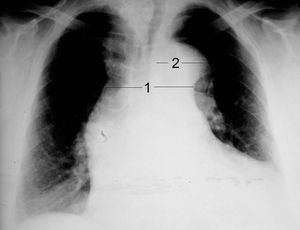

흉부 방사선 촬영은 대동맥 박리에서 나타날 수 있는 흉부 대동맥의 형태 변화를 보여줄 수 있다. 전형적으로, 방사선 사진에서 종격동의 새로운 확장 소견은 상행 대동맥 박리를 감지하는 데 중간 정도의 민감도를 보이지만, 다른 많은 질환이 종격동의 명백한 확장을 유발할 수 있으므로 이 소견은 특이도가 낮다.

다음과 같은 다른 방사선학적 소견들이 관련되어 있다.

- "칼슘 징후"는 내막 석회화가 외부 대동맥 가장자리에서 10mm 이상 분리된 것처럼 보이는 것을 나타낸다.

- 흉수는 하행 대동맥 박리에서 더 흔하게 나타나며, 전형적으로 좌측에 발생한다.

- 기타 소견: 대동맥 융기 소실, 좌측 주 기관지 압박, 기관 주위 선 소실, 기관 편위.

중요한 것은, 대동맥 박리의 약 12~20%는 흉부 방사선 사진으로 감지할 수 없다는 것이다. 따라서 "정상" 흉부 방사선 사진은 대동맥 박리를 배제하지 못한다. 임상적 의심이 높은 경우, 보다 민감한 영상 검사(컴퓨터 단층 촬영 혈관 조영술, 자기 공명 혈관 조영술, 또는 경식도 심장 초음파)가 필요할 수 있다.